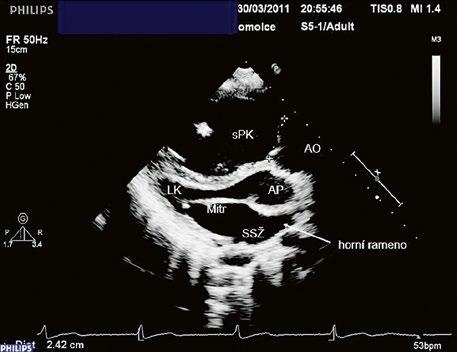

Poslechový nález systolického šelestu nad plicnicí s fixním rozštěpem 2. ozvy je nenápadný. Echokardiograficky je patrná dilatovaná a objemově přetížená pravá komora s paradoxním pohybem septa (Obr. 45.9), zkratový tok může být vidět i transtorakálně (TTE) (Obr. 45.10, Video 45.3, Video 45.7), ale suverénní diagnostickou metodou je jícnová echokardiografie (TEE), případně s 3DE zobrazením (Obr. 45.1, Obr. 45.2,

Obr. 45.10 TTE, čtyřdutinová apikální projekce s levo pravým zkratem na úrovni síní (šipka) při defektu septa síní typu secundum PK – pravá komora, LK – levá komora, LS – levá síň, PS – pravá síň